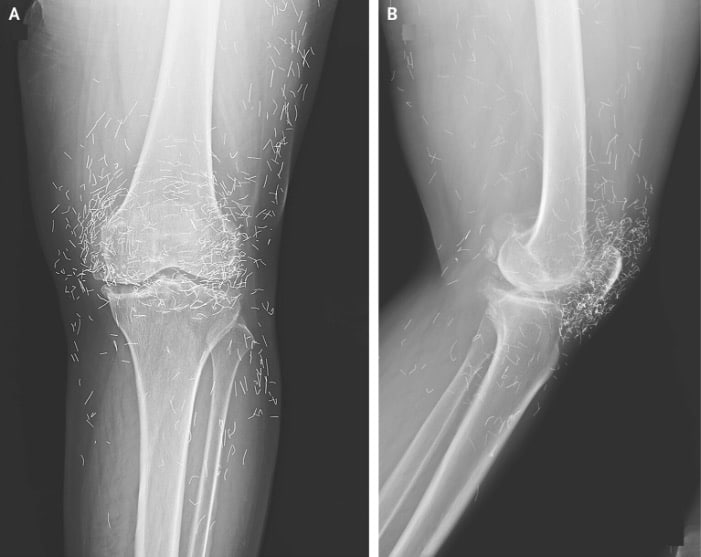

Years later, when doctors took X-rays to evaluate her knee condition, they weren’t prepared for what appeared on the images. Her knees were filled with dozens of bright, metallic flecks — tiny needles embedded deep within the joint area.

The findings were later documented in a case published by the New England Journal of Medicine.